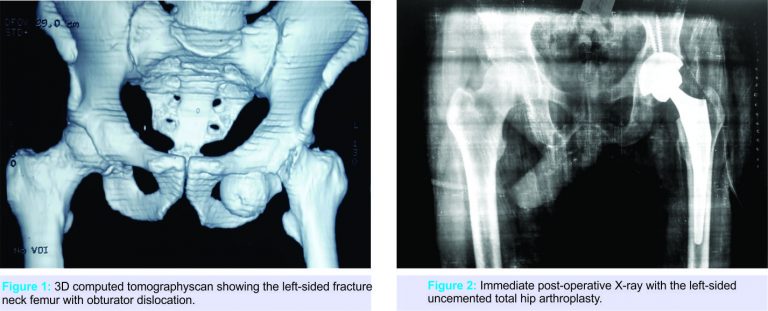

A 32-year-old male patient was brought to the emergency department following a road traffic accident. He was driving two wheeler and sustained a head-on collision with four wheeler resulting in sudden halt and fall from the bike. His hip was in flexion, abduction, and external rotation with shortening of the affected leg. After initial stabilization and examination, radiographs were done which showed an obturator type anterior dislocation with fracture neck of the femur. Computed tomography scan was done to rule out for any acetabulum fracture and any other associated injury (Fig. 1).

Patient and family members were consulted and detailed discussion was done regarding the type of injury and the possible treatment options. After knowing all the treatment options and their prognosis, the patient was more inclined toward undergoing a single surgery. After admission, definitive treatment was carried out within about 10 h of injury. A lateral skin incision was made starting from distal and lateral to anterosuperioriliac spine and curved distally and posteriorly over the greater trochanter. Interval between gluteus medius and tensor fascia lata was located (Watson-Jones approach). The anterior capsule was incised longitudinally. Acetabulum was found to be empty. A button hole through the anterior-inferiorcapsule was noted. The head and neck found to be dislocated and lying close to obturator foreman. Head and neck was retrieved and the articular surface of the femoral head showed the medium-sized chondral defect. Keeping in mind the size of chondral defect, the decision was made to perform an uncemented total hip arthroplasty. An uncemented total hip arthroplasty was performed with standard surgical technique (Fig. 2). Post-operative period was uneventful and the patient was mobilized weight-bearing as tolerated with walker. He was discharged on the 5th post-operative day. He regained pain-free good range of motion over a period of 6 weeks.